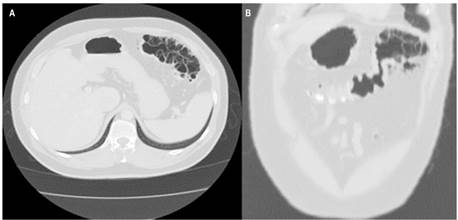

Se trata de un paciente masculino de 35 años de edad que consultó por un cuadro clínico de un mes de evolución de dolor de alta intensidad, inespecífico, localizado en el hemiabdomen inferior, con irradiación a la región lumbar derecha, sin desarrollo clínico de abdomen agudo. Tuvo un diagnóstico inicial de infección de las vías urinarias y tratamiento con levofloxacina ambulatoriamente, pero ante la no mejoría de los síntomas, el paciente volvió a consultar. Se realizó una tomografía axial computarizada (TAC) contrastada de abdomen, en la que se evidenció una neumatosis intestinal quística segmentaria en el ángulo esplénico del colon asociado con áreas de neumoperitoneo adyacentes (Figura 1). Fue valorado por el servicio de cirugía general, en el que se inició el manejo con laparoscopia y se encontró plastrón con epiplón y neumatosis en el ángulo esplénico, por lo que convierten el procedimiento inicial a una laparotomía, en la que decidieron realizar hemicolectomía izquierda, omentectomía parcial y colostomía izquierda.